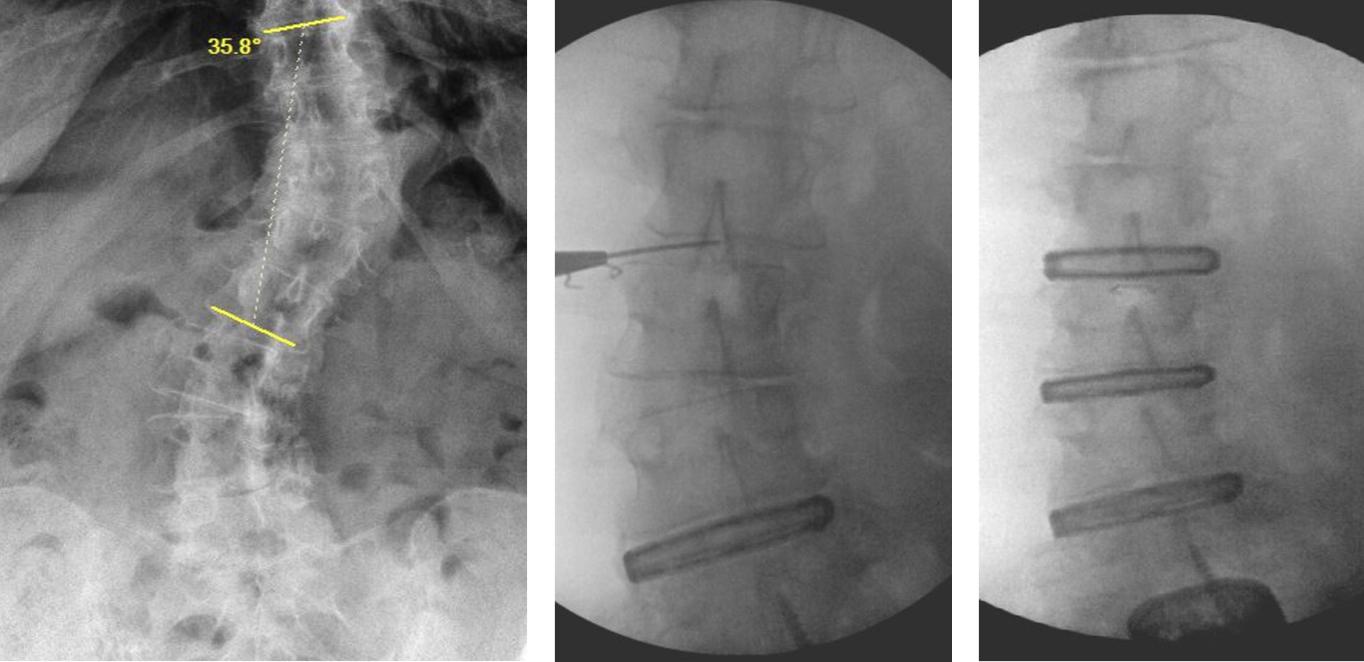

Before:

Scoliosis Correction:

- In some cases as the lumbar discs degenerate they collapse more on one side creating angular deformity and scoliosis (curvature of the spine).

- Placing the cages creates a parallel space between the bones, correcting the scoliosis.

- Further correction of the scoliosis is achieved with the screws and rods.